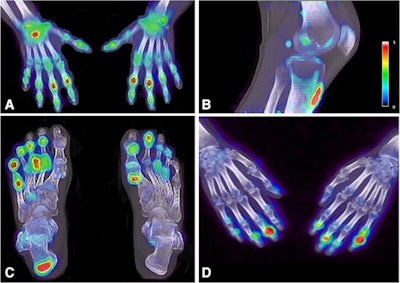

F-18 sodium fluoride (NaF) PET/CT may be a valuable tool for imaging patients with psoriatic arthritis (PsA), as it reveals new bone formation in peripheral joints missed on clinical evaluation, according to a Dutch group.

"F-18 NaF PET/CT may be a novel clinically valuable tool to detect whole-body disease activity of PsA reflected by new bone formation in all disease domains of PsA, depicted in one scan," a team led by doctoral candidate Jerney de Jongh wrote. The study was published November 12 in the European Journal of Nuclear Medicine and Molecular Imaging.

In this study, the researchers enrolled 16 patients with a clinical diagnosis of psoriatic arthritis from a rheumatology center at Amsterdam UMC. Patients underwent whole-body PET/CT scans 45 minutes after injection with F-18 NaF, a radiotracer that can identify new bone formation based on osteoblastic activity.

According to the study results, 81.8% of PET-positive joints were missed on clinical assessment. The team found that only 18.2% of PET-positive joints were clinically positive (that is, tender or swollen). But most PET-negative sites were also clinically negative (611/638). Similar results were found for entheses, with 70.5% of the PET-positive entheses missed on clinical evaluation and 29.5% of PET-positive entheses clinically identified.